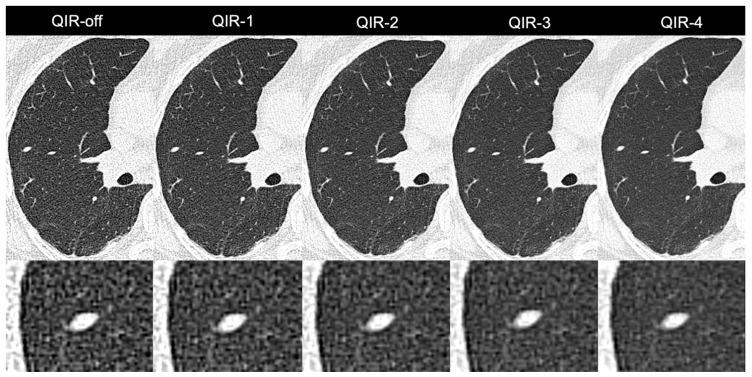

The aim of this study was to characterize image quality and to determine the optimal strength levels of a novel iterative reconstruction algorithm (quantum iterative reconstruction, QIR) for low-dose, ultra-high-resolution (UHR) photon-counting detector CT (PCD-CT) of the lung. Images were acquired on a clinical dual-source PCD-CT in the UHR mode and reconstructed with a sharp lung reconstruction kernel at different strength levels of QIR (QIR-1 to QIR-4) and without QIR (QIR-off). Noise power spectrum (NPS) and target transfer function (TTF) were analyzed in a cylindrical phantom. 52 consecutive patients referred for low-dose UHR chest PCD-CT were included (CTDI: 1 ± 0.6 mGy). Quantitative image quality analysis was performed computationally which included the calculation of the global noise index (GNI) and the global signal-to-noise ratio index (GSNRI). The mean attenuation of the lung parenchyma was measured. Two readers graded images qualitatively in terms of overall image quality, image sharpness, and subjective image noise using 5-point Likert scales. In the phantom, an increase in the QIR level slightly decreased spatial resolution and considerably decreased noise amplitude without affecting the frequency content. In patients, GNI decreased from QIR-off (202 ± 34 HU) to QIR-4 (106 ± 18 HU) ( < 0.001) by 48%. GSNRI increased from QIR-off (4.4 ± 0.8) to QIR-4 (8.2 ± 1.6) ( < 0.001) by 87%. Attenuation of lung parenchyma was highly comparable among reconstructions (QIR-off: -849 ± 53 HU to QIR-4: -853 ± 52 HU, < 0.001). Subjective noise was best in QIR-4 ( < 0.001), while QIR-3 was best for sharpness and overall image quality ( < 0.001). Thus, our phantom and patient study indicates that QIR-3 provides the optimal iterative reconstruction level for low-dose, UHR PCD-CT of the lungs.

本研究的目的是对图像质量进行表征,并确定一种新型迭代重建算法(量子迭代重建,QIR)在肺部低剂量、超高分辨率(UHR)光子计数探测器CT(PCD-CT)中的最佳强度水平。在临床双源PCD-CT上以UHR模式采集图像,并使用锐利的肺部重建内核在不同强度水平的QIR(QIR-1至QIR-4)下以及不使用QIR(QIR-off)进行重建。在圆柱形体模中分析噪声功率谱(NPS)和目标传递函数(TTF)。纳入了52例连续接受低剂量UHR胸部PCD-CT检查的患者(CTDI:1±0.6 mGy)。通过计算进行定量图像质量分析,包括计算全局噪声指数(GNI)和全局信噪比指数(GSNRI)。测量肺实质的平均衰减。两名阅片者使用5分李克特量表对图像的整体图像质量、图像清晰度和主观图像噪声进行定性评分。在体模中,QIR水平的增加会使空间分辨率略有下降,噪声幅度显著降低,而不影响频率成分。在患者中,GNI从QIR-off(202±34 HU)降至QIR-4(106±18 HU)(<0.001),降幅为48%。GSNRI从QIR-off(4.4±0.8)增至QIR-4(8.2±1.6)(<0.001),增幅为87%。肺实质的衰减在各重建图像之间具有高度可比性(QIR-off:-849±53 HU至QIR-4:-853±52 HU,<0.001)。主观噪声在QIR-4时最佳(<0.001),而QIR-3在清晰度和整体图像质量方面最佳(<0.001)。因此,我们的体模和患者研究表明,QIR-3为肺部低剂量、UHR PCD-CT提供了最佳的迭代重建水平。